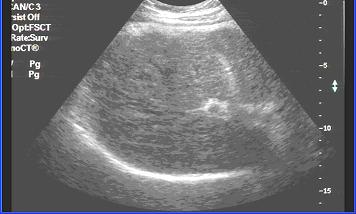

一、慢性肝炎炎症活动期时超声影像:

炎性期肝脏肿大、胆囊壁水肿。